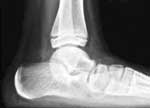

Le cliché de profil en charge est fort utile. Il permet de mettre en évidence plusieurs signes secondaires( Fig.11 et 12), mais doit être interprété avec prudence et de manière comparée. Les rares synostoses de la facette postérieure et de l’os trigone peuvent parfois s’observer sous la forme d’une masse localisée (28).

Par contre, il est souvent insuffisant dans les formes TC. Il est alors utile de réaliser une incidence axiale postérieure de l’arrière pied décrite par KORVIN en 1934 et popularisée par HARRIS et BEATH. Elle permet de visualiser directement la synostose de la facette moyenne ou met en évidence une série de signes secondaires très évocateurs :

• élargissement ou hypoplasie du sustentaculum tali ;

• obliquité et inclinaison caudale de la facette moyenne qui normalement est parallèle à la facette postérieure. Si cette inclinaison est > à 25° par rapport à la facette postérieure, il s’agit d’un signe de certitude (15) ;

• pincement et irrégularités de l’interligne articulaire.

Cette incidence est la plus fiable pour le diagnostic des synostoses TC (54) mais ne permet pas le dépistage de tous les cas. Elle est aujourd’hui largement supplantée par le CT-scan et l’IRM dans cette indication.

a) Le signe de l’anneau ou « C-sign »

Ce signe décrit par LATEUR (33) et l’équipe de la K.U.L. en 1994 est une ligne en forme de C formée par le bord médial du dôme talien et le bord caudal du sustentaculum tali sur une radiographie du pied de profil en charge (Fig.12). Dans une double étude rétrospective (18 cas) et prospective (15 cas), les auteurs montrent que ce signe radiologique est spécifique, dans 93,3 % des cas, de la présence d’une synostose TC. La sensibilité est de 86,6 %. La visibilité, l’importance et la régularité de ce signe varie en fonction de la forme et de la taille du sustentaculum tali. Ce signe est parfois fort discret ou absent en cas d’hypo- ou d’aplasie du sustentaculum. Dans l’étude prospective, 10 patients sur 15 avaient un signe positif mais sans point d’appel clinique, ce qui amène les auteurs à considérer qu’il s’agit du signe secondaire le plus fiable dans les synostoses TC.

Cet enthousiasme doit être nuancé par la découverte ultérieure de faux positifs liés à des pieds plats sévères et par le travail de BROWN (7), publié en 2001 dans lequel il observe que le signe de l’anneau est plus spécifique d’un pied plat que d’une synostose avec une sensibilité assez faible (33 %).